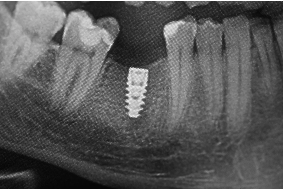

Implant to niewielkich rozmiarów śrubka, która wszczepiona w kość szczęki lub żuchwy zastępuje funkcję utraconego korzenia zęba. Implanty zębów produkowane są najczęściej z tytanu. To bezpieczny i biozgodny dla naszego organizmu materiał, który cechuje dodatkowo duża wytrzymałość mechaniczna. Pozwala to na prawidłowe zrośniecie się implantu z kością, a po wgojeniu – na trwałe umocowanie rekonstrukcji korony brakującego zęba.

pierwszy implant z tytanu

Tytanowe implanty stomatologiczne zostały eksperymentalnie wszczepione w kość pacjenta po raz pierwszy w roku 1965. Autorem i pomysłodawcą tej techniki był pochodzący ze Szwecji Profesor medycyny Per Ingvar Branemark. Od tego czasu trwają nieprzerwane prace badawcze na całym świecie nad rozwiązaniami, które w szybki, trwały i niezawodny sposób odtwarzają anatomię i funkcję naszego organizmu.

Obecnie implanty zębowe stanowią podstawę współczesnej rehabilitacji protetycznej w stomatologii i są dostępne dla każdego pacjenta bez ograniczeń wiekowych. Z perspektywy lat i osiągnięć medycyny XX wieku bezcenne są biologiczne, funkcjonalne i medyczne skutki ich zastosowania.